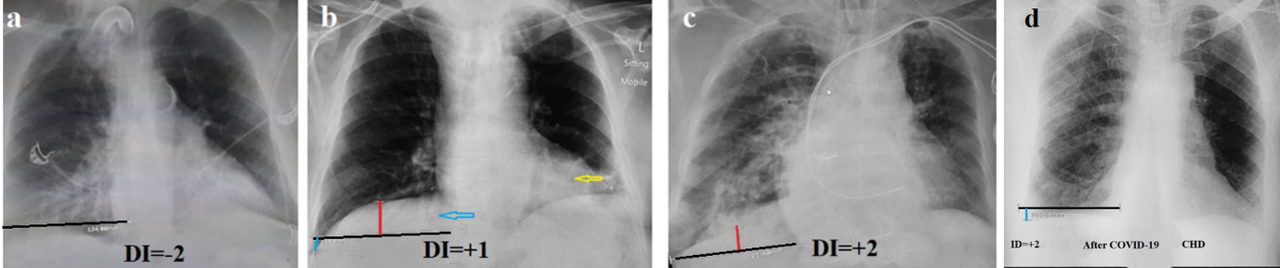

In the 2nd group among 25 patients the DI ranged from -2 to (+18) (average 2.6) (Figure 3). In these patients, respiratory failure was due to either cardiac failure (8) or a decrease in lung volume due to atelectasis (12). Tumor-related atelectasis occurred in 3 cases. In addition, restrictive processes occurred in 4 cases, including 2 patients with COVID-19.

Figure 3. Radiographs of patients with respiratory failure in whom COPD was excluded by the proposed method. (a) Atelectasis of the lower left lobe and bronchiectasis in the right lower lobe. (b). The patient was admitted with a diagnosis of COPD exacerbation. The lung volume has not increased. DI= +1. The blue arrow shows bronchiectasis in the lower lobe on the right, and the yellow arrow shows atelectasis above the left diaphragm. (c). In a patient with chronic heart disease who suffered a pulmonary embolism. (d). CHD. The decreased volume and increased transparency of the left lung is due to atelectasis of the lower lobe in a patient after COVID-19.

In the 2nd group, the causes of respiratory failure were restrictive causes: atelectasis, bronchiectasis, conditions after pulmonary embolism, heart failure etc. We do not have data on the basis (research methods) by which COPD was diagnosed in the patients of the second group at the hospitals from which they arrived. An analysis of various diagnostic methods COPD will be provided in the "Discussion" section.